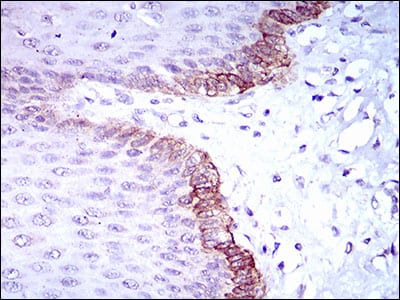

分类: 科研抗体货号: 30509别名: IRIS; PSCP; BRCAI; BRCC1; PNCA4; RNF53; BROVCA1; PPP1R53应用: IHC反应种属: Human